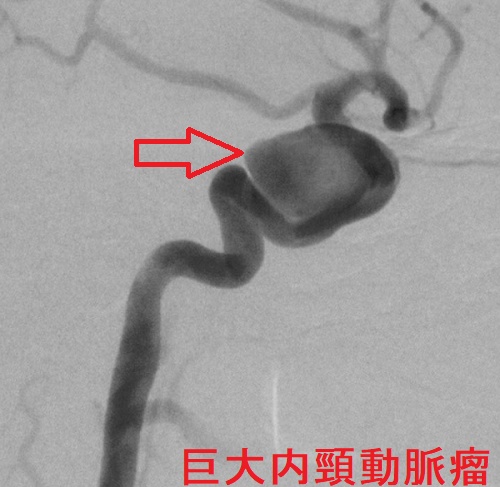

内頸動脈瘤

内頸動脈瘤も内頸動脈-後交通動脈分岐部動脈瘤(IC-PC 動脈瘤)と同じく、動眼神経麻痺を起こします。さらには、滑車神経・外転神経麻痺による複視や三叉神経第1枝・第2枝の圧迫による顔面の知覚障害を伴う場合も。

内頸動脈瘤が破裂した場合、海綿静脈洞内に血液が流れ込むので、くも膜下出血に至りません。しかし、海綿静脈洞内の静脈圧が上昇し、上眼静脈へ逆流するため、眼球突出を来します。ただし、拍動する眼球突出なので、甲状腺眼症(バセドウ病眼症・橋本病眼症)と異なります。